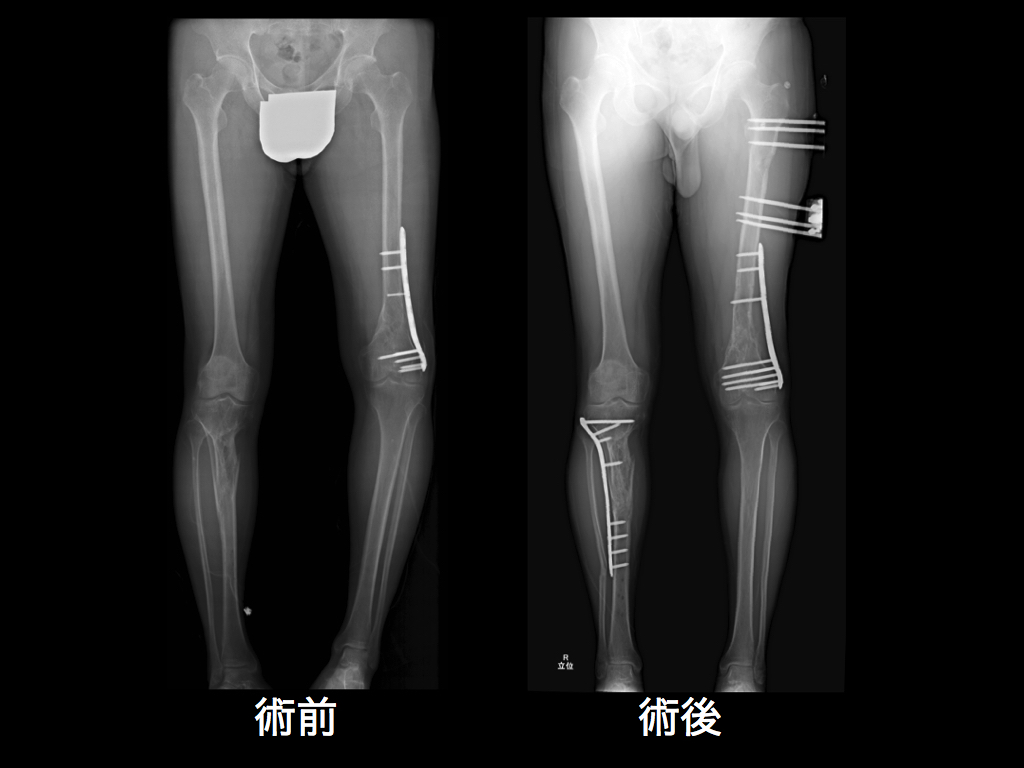

fu6434928.jpg

>fu6434928.jpg

術後チンポでっか

こういう手術はCアームでリアルタイムに骨折部位を確認しながら手術を進めることになるが被曝によるリスク(一時的な不妊の可能性)よりも骨折を治して歩けるようになることがどう考えても遥かに有益だからな